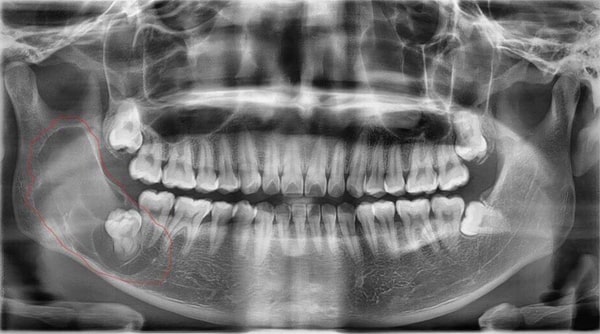

Nhổ răng khôn hay răng số 8 là một quá trình thực hiện bóc tách bác mô nướu, dùng dao chuyên dụng thực hiện mở xương hàm để lấy răng khôn hoặc nhổ nhiều chiếc răng khôn của bạn.

Tuy không phải là một phương pháp yêu cầu kỹ thuật quá phức tạp, tuy nhiên vẫn có một số biến chứng và rủi ro có thể xảy ra nếu quy trình thực hiện nhổ răng khôn của bạn không đảm bảo hoặc chăm sóc sai cách tại nhà. Điển hình trong số đó, phải đặc biệt kể đến tình trạng vị trí nhổ răng bị nhiễm trùng sau khi nhổ răng khôn, nguy hiểm sẽ dẫn đến tình trạng nhiễm trùng máu.

2.4 Trình độ tay nghề của bác sĩ thực hiện nhổ răng 8

Dù biết kỹ thuật nhổ răng khôn không quá phức tạp và đa phần các bác sĩ chuyên khoa đều có thể thực hiện được. Nhưng, nếu bác sĩ tay nghề kém, không nắm vững kiến thức chuyên môn thì sẽ rất nguy hiểm cho bạn, bởi những dấu hiệu bất thường có thể xảy ra trong lúc nhổ sẽ không được xử lý kịp thời và đúng cách, gây ra những ảnh hưởng nghiêm trọng mà bạn không lường trước được.